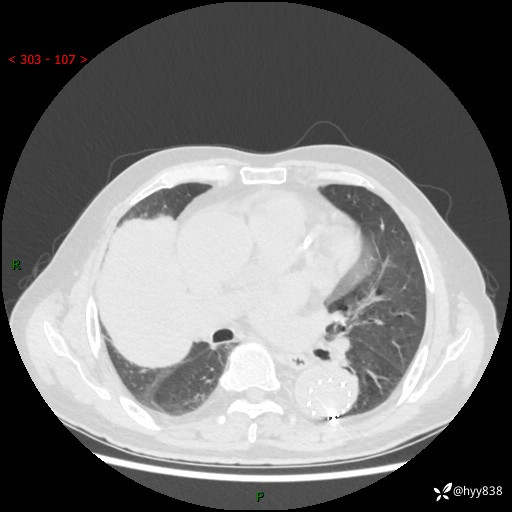

辅助检查:CT

胸部CT平扫